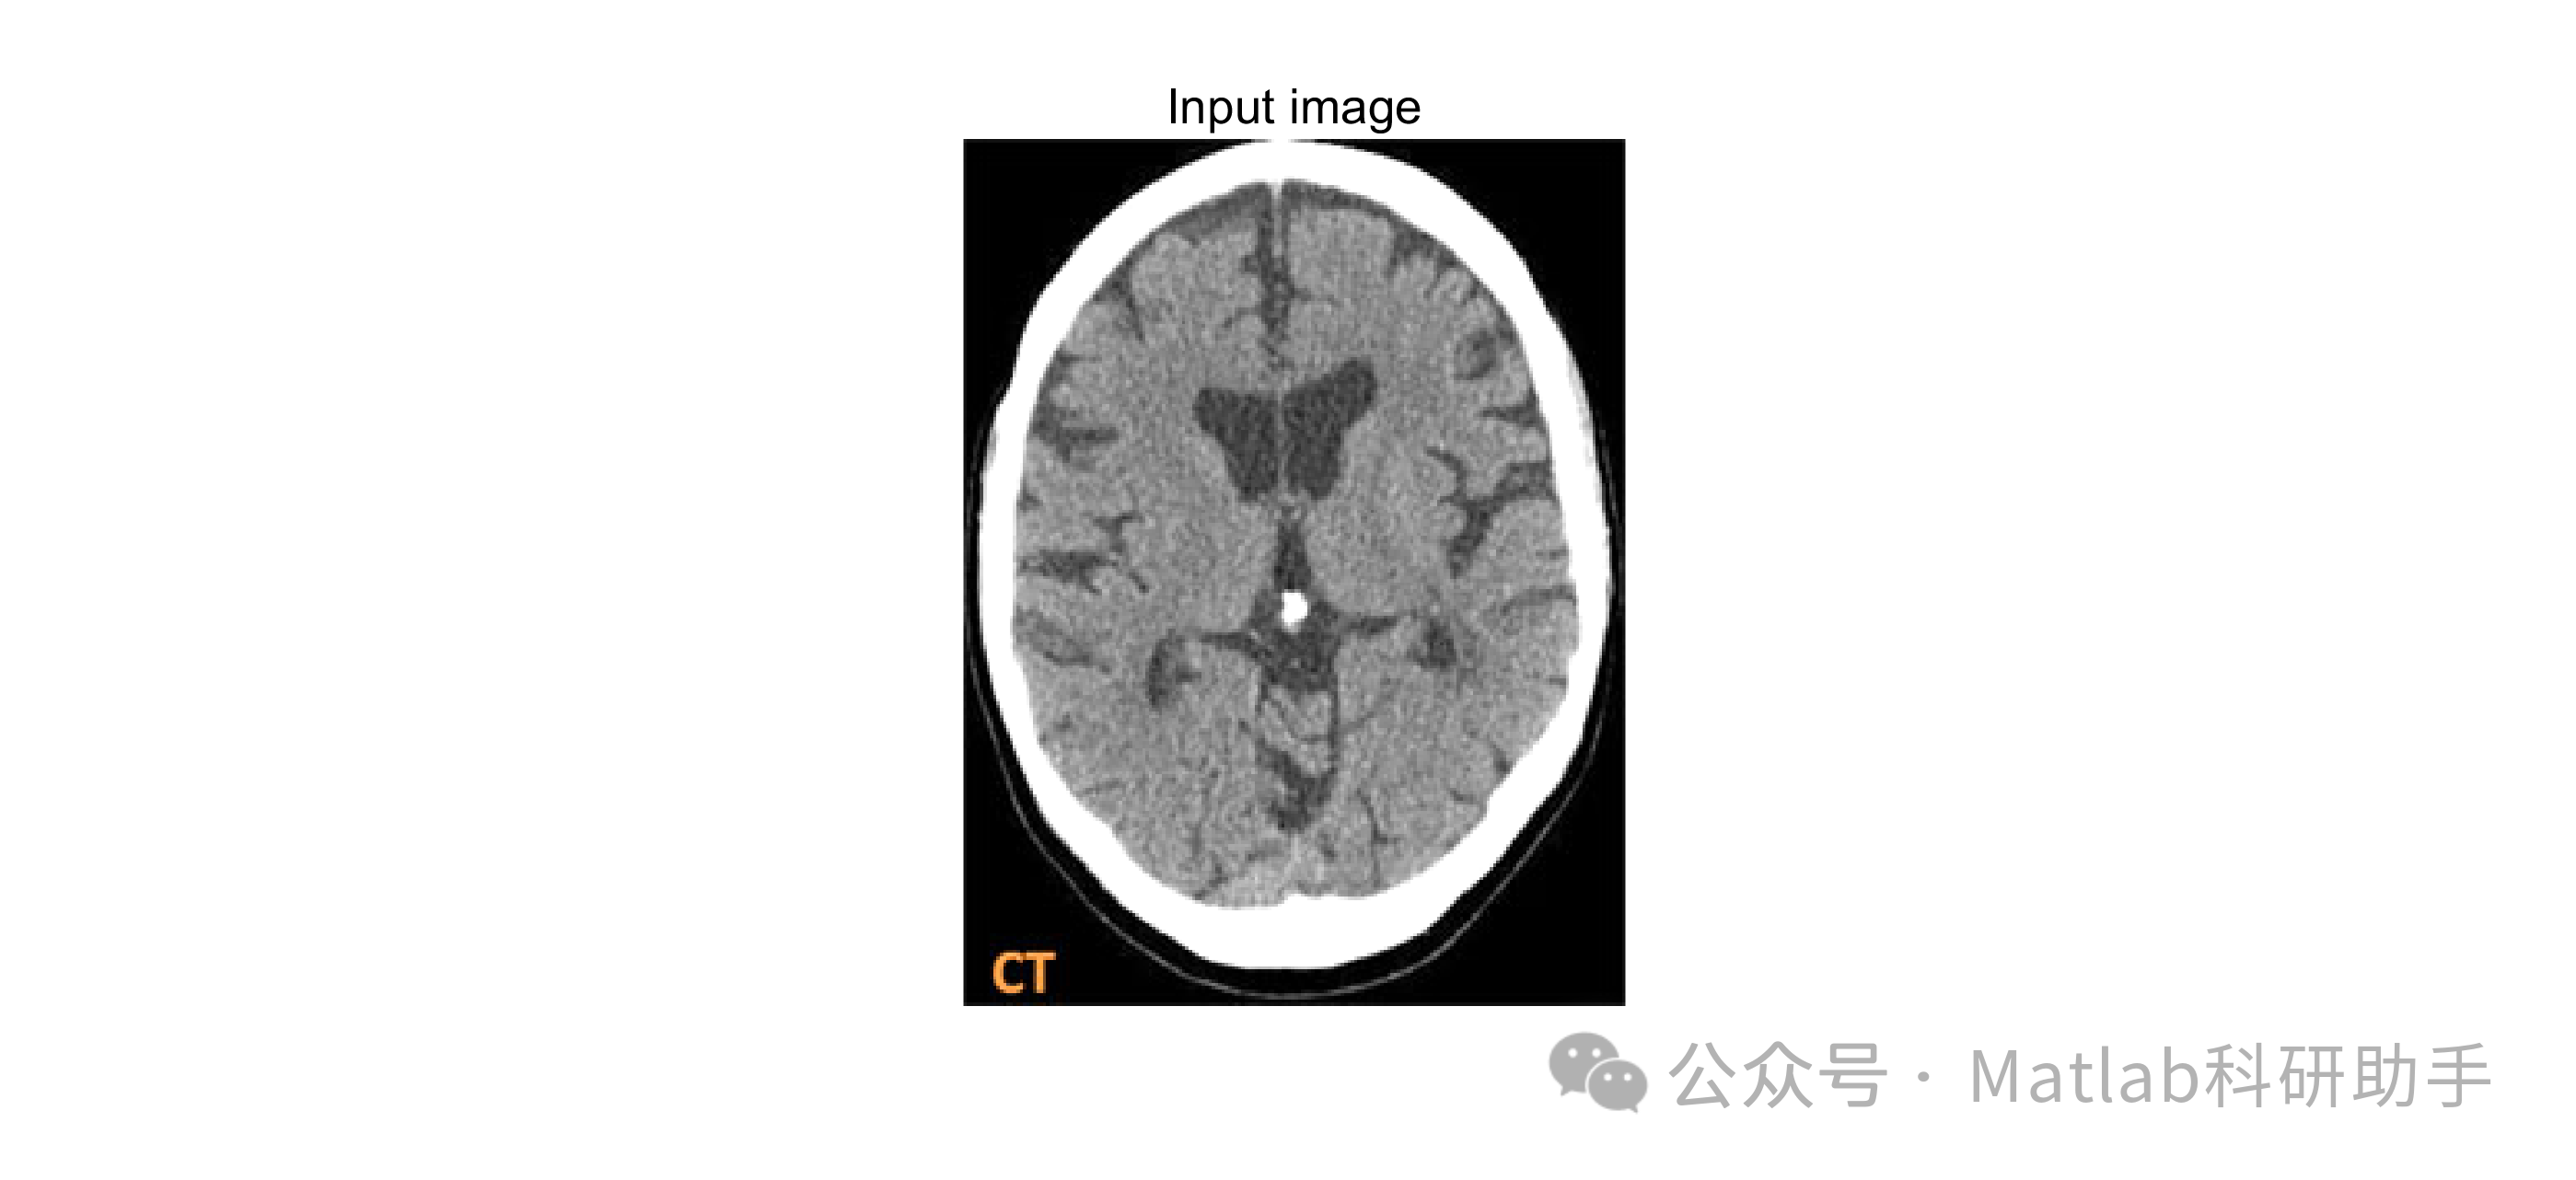

⛳️ 运行结果

一个典型的基于各向异性滤波与图像分割的MRI脑肿瘤检测流程如下:

- 图像预处理:

读取MRI图像,进行灰度化处理。

利用各向异性滤波器(如Perona-Malik滤波器或Weickert滤波器)对图像进行去噪和平滑处理。 选取合适的参数K和迭代次数,以达到最佳的去噪效果和边缘保留能力。

进行图像标准化或归一化,将图像灰度值范围调整到0-1之间,方便后续处理。